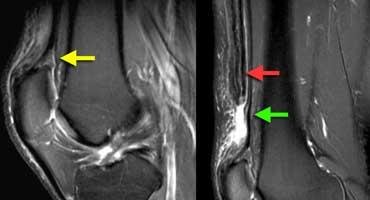

TRÁI: Nang khoeo xuất phát giữa gân cơ bán màng (mũi tên đỏ) và cơ cùng gân cơ sinh đôi (mũi tên xanh lá). PHẢI: Nang khoeo vỡ với dịch lan dọc theo các cơ.

Ngách khớp phổ biến nhất là nang khoeo hay còn gọi là nang Baker.

Vị trí xuất phát nằm giữa gân cơ bán màng và gân cơ sinh đôi.

Hội chứng ma sát dải chậu chày: Dịch trong túi hoạt dịch thấy được giữa dải chậu chày và xương đùi (mũi tên vàng). Dịch khớp dừng lại tại các mũi tên đỏ.

Cùng bệnh nhân trên. Trên các lát cắt axial, có thể thấy dịch trong túi hoạt dịch nằm giữa dải chậu chày và xương đùi bên dưới.

Đôi khi cần phân biệt dịch tại vị trí này với dịch khớp.

Cần xem xét toàn bộ các lát cắt hình ảnh.

Trong trường hợp này, dịch khớp dừng lại tại các mũi tên đỏ.